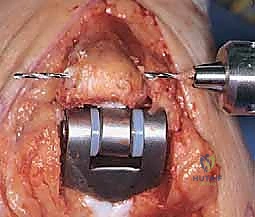

يتم إبعاد العضلات والأربطة بلطف للوصول إلى المفصل. يقوم الجراح بإزالة الغشاء الزليلي الملتهب بالكامل (Synovectomy)، ثم يزيل الأسطح العظمية المتآكلة من نهايات عظم العضد وعظم الزند باستخدام أدوات جراحية دقيقة جداً.

يتم بعد ذلك حفر القناة النخاعية داخل عظم العضد وعظم الزند لتجهيز المساحة التي سيتم إدخال سيقان المفصل الصناعي فيها.

5. زراعة المفصل الصناعي (Implantation)

يتكون المفصل الصناعي من قطعتين معدنيتين رئيسيتين (جزء عضدي وجزء زندي) وبينهما مفصلة بلاستيكية (Hinge) توفر الحركة السلسة.

يتم تثبيت هذه الأجزاء المعدنية داخل القنوات العظمية باستخدام الأسمنت العظمي الطبي (Bone Cement)، وهو مادة خاصة تضمن تثبيتاً فورياً وقوياً، وهو أمر بالغ الأهمية لمرضى الروماتويد الذين يعانون من هشاشة العظام.